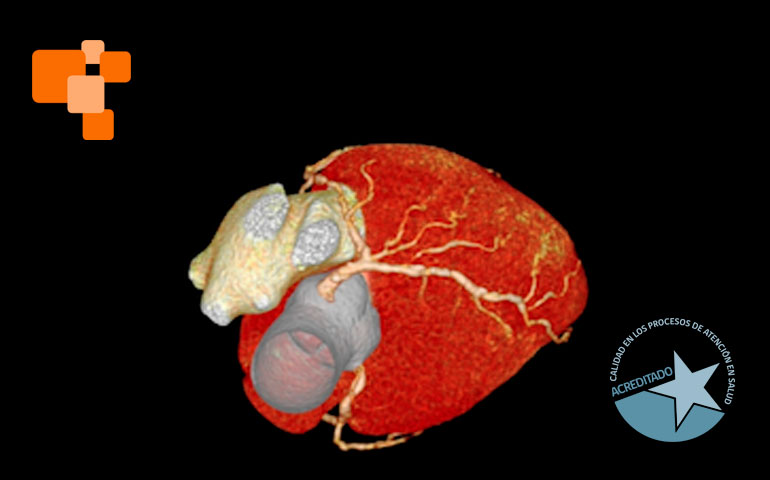

El rol de TAC de calcio coronario

La preparación para un TAC de calcio coronario es mínima, lo que lo hace un procedimiento conveniente para muchos pacientes. Según sea su resultado, permiten a los profesionales de la salud recomendar cambios de estilo de vida o tratamientos adecuados para reducir el riesgo de enfermedad cardíaca.